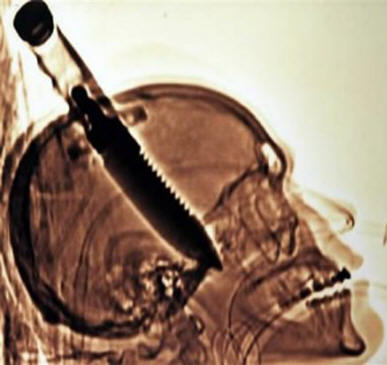

V roce 1998 navštívil Michael Hill s přítelem na Floridě, když najednou na ulici šel k němu blázen a … bez důvodu bez důvodu ho uvízl v holém noži. Sám Michael se vrátil domů, správně s madlem vyčnívajícím z mé hlavy a jen tam šokován přítel zavolal sanitku. Hill to později řekl téměř necítil bolest v hlavě (i když to tomografie ukázala) nůž pronikl mozkem asi o 20 cm!), jediná věc, kterou on poznamenal, že toto je „teplo v pravém oku“. Po čtyřech hodinách operace Michael byl již převeden na oddělení ao pár dní později vybitý. Nakonec byla levá ruka toho chlapa ochrnutá, ale doktoři říkají, že stále snadno vystoupil.